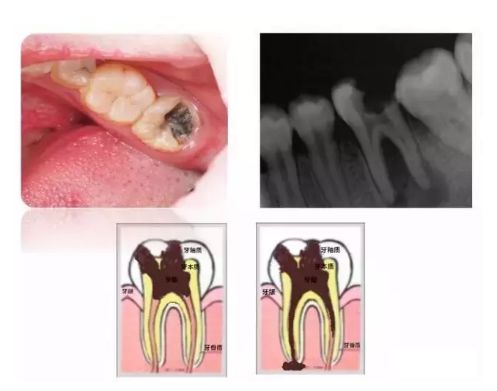

当龋坏累及牙髓

深龋再往下发展会变成什么呢?当龋坏累及到牙神经,就会引发牙神经发炎和牙根发炎,我们称之为牙髓炎和根尖周炎。这时候疼痛会更剧烈,情况就比较严重了,治疗手段也会变得更复杂。所以说“小洞不补,大洞吃苦”,一发现龋齿就要去牙科检查。